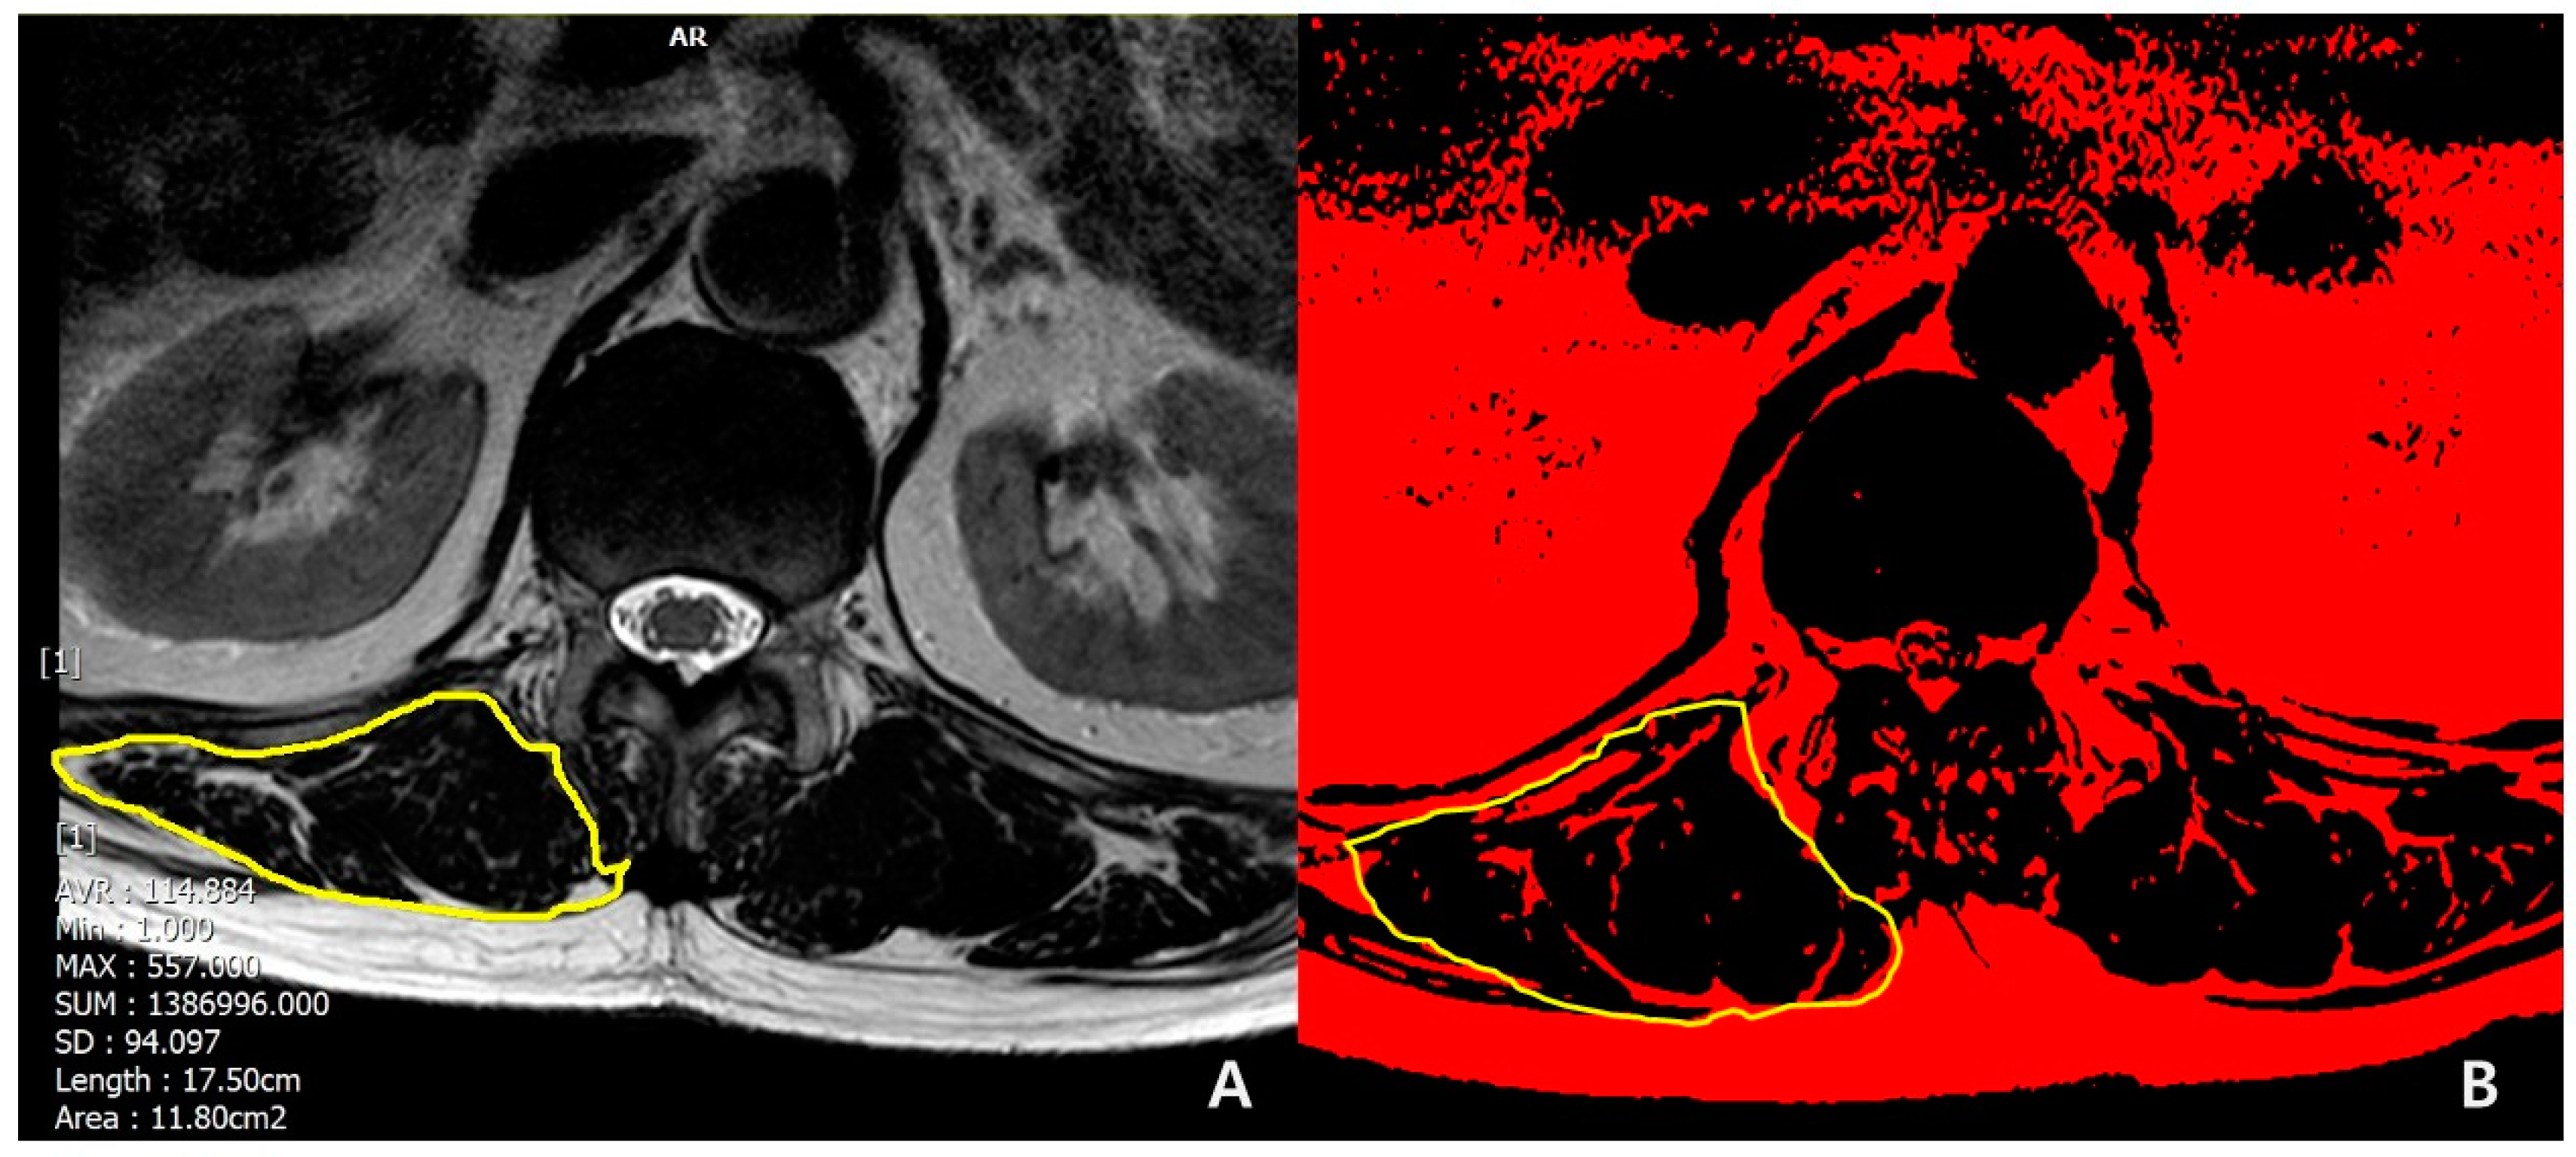

The following demographic and surgical data were collected: age at surgery ; sex (female/male); bone mineral density (BMD, T-score); body mass index (BMI, kg/m2); smoking; previous spinal fusion; American Society of Anesthesiologist physical status (ASA) grading; iliac fixation; disc degeneration by Pfirrmann grade [16] at T12-L1 segment (1,2,3: mild to moderate; 4,5: severe); muscularity status at T12-L1 (cross-sectional area [CSA], cm2) and fat infiltration grade (mild to moderate, if <50%; severe, if ≥ 50%) in erector spinae muscle at T12-L1 in T2-weighted axial magnetic resonance (MR) images using Picture Archiving and Communication System (PACS) by Philips ACHIEVA 3.0T (Philips Healthcare, UK) and the ImageJ software. The region of interest (ROI) for erector spinae muscle at T12-L1 level was outlined polygonally with manipulation of graphic cursor and handled with pseudocoloring method.[17] (Figure 1) Then, CSA (Figure 1A) were calculated and fat infiltration grade (Figure 1B) was determined.

Figure 2. Methods for measuring A) CSA and B) FI of erector spinae muscle.

In univariate analysis of demographics, PJK group showed more frequent in female (100% in PJK vs 73% in non-PJK, p=0.011), osteoporosis (60.9% in PJK vs 12.1% in non-PJK, p<0.001). Also, PJK group showed the lower mean value of the lowest T-score in BMD (-2.4 ± 0.8 in PJK vs -1.5 ± 1.1 in non-PJK, p=0.006) and BMI (24.4 ± 2.4 in PJK vs 27.1 ± 4.3 in non-PJK, p=0.004) with statistical significance. In comparison of muscular quantity between the groups, there were smaller CSA (cm2, 23.8 ± 4.2 vs 32.2 ± 10.1, p<0.001) in erector spinae muscle at T12-L1 in PJK group than non-PJK group. Also, in comparison of muscular quality between the groups, PJK group showed more frequent severe (≥50%) fat infiltration in erector spinae muscle at T12-L1 with statistical significance (p<0.001) (Table 3) (Figure 4 and Figure 5).

Figure 4. A case of 66-year old female patient with PJK. A) Preoperative axial T2-weighted magnetic resonance image showing erector spinae muscle with severe (>50%) fat infiltration at T12-L1 level. B) Preoperative BMD showing osteoporosis. C) Preoperative whole spine standing lateral radiograph showing PJA of 5.37˚. D) Postoperative 3-month standing lateral whole spine radiograph showing PJA of 10.42˚. E) Postoperative 2-year standing lateral whole spine radiograph showing PJK (PJA of 28.17˚) with increased C7SVA.